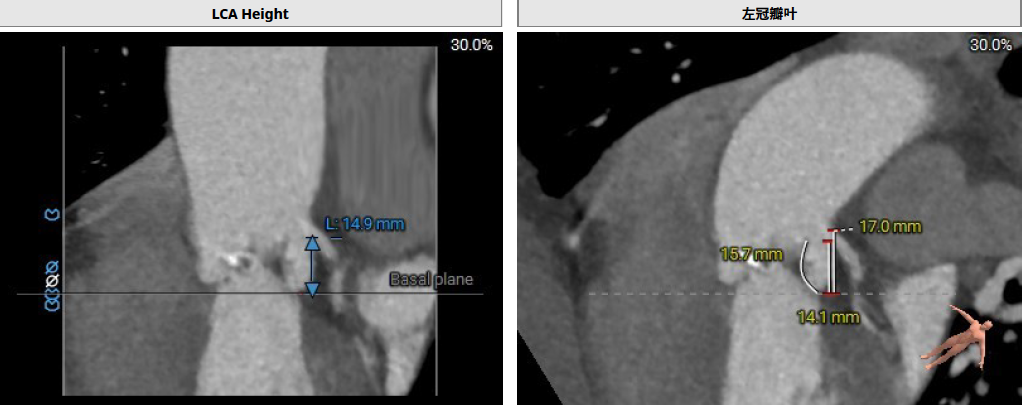

患者Type1 二叶瓣,右无融合,融合嵴钙化,钙化主要分布瓣叶缘和融合嵴处,无冠窦底钙化向下延伸至流出道4mm处。Annulus面积398mm²,LVOT面积400mm²,SOV 27.6-30.9mm,STJ高度21.3mm,内径29-32.7mm,瓣环角度62°,升主动脉扩张,左冠高度14.9mm,左冠瓣叶长度15.7mm,右冠高度15.8mm,右冠瓣叶长度9.2mm,模拟植入21#瓣膜VTC LCA 2.4mm,右侧髂内分叉处可见钙化,右侧髂外动脉最细为6.1mm,左侧髂外动脉最细为6.1mm,外周入路尚可。

左冠高度:High: 14.9mm

右冠高度:High: 15.8mm

左冠高度14.9mm,左冠瓣叶长度15.7mm,右冠高度15.8mm,右冠瓣叶长度9.2mm,模拟植入21#瓣膜VTC LCA 2.4mm